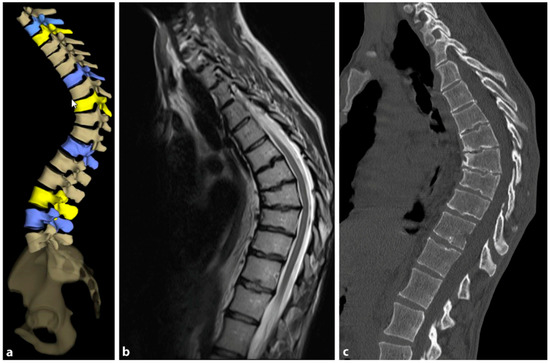

The need for MRI diagnosis has been demonstrated in several studies. In a recent study, the prevalence of syringomyelia was found to be 5.8% in patients with SD [89]. MRI is an obligatory preoperative preparation to exclude myelon compression, thoracic disc herniation, or spinal canal stenosis. Figure 9 provides a comparative visualization of thoracic SD captured through different imaging techniques: stereoradiography, MRI, and computer tomography (CT).

4.2. Diagnostics

Although initially described by Sorensen, the definition of SD has been definitively established by subsequent work by Edgren et al. and Blumenthal et al., with SD typically manifesting mostly in the thoracic spine (type I) and less commonly in the lumbar spine (type II) [79,85,86]; see Figure 7. The measurement of thoracic kyphosis according to Cobb (Th1–Th12) is sometimes difficult on conventional X-rays due to the humeral heads, so the Stagnara angle (Th4–Th12) is a reliable alternative (Figure 8). In children with SD, back pain and a positive family history are common, and clinical examination typically reveals a gibbus and a flexible deformity. In addition to a detailed medical history, a thorough physical examination is of utmost importance. The various signs and findings typical of SD are listed in Table 2.